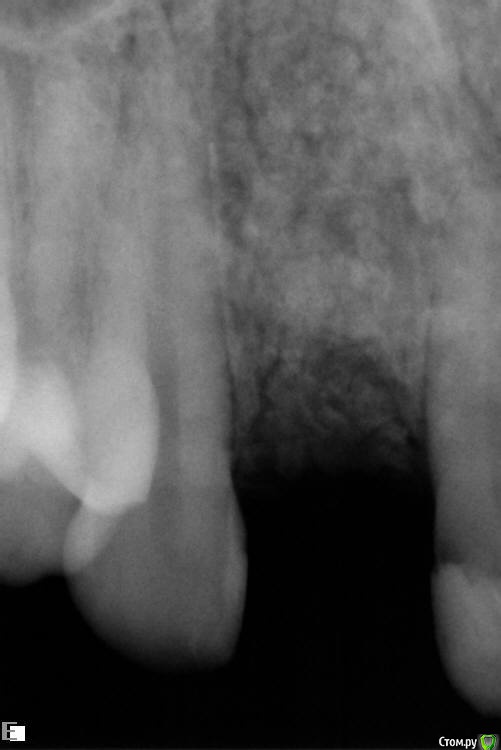

Slaggy Опубликовано 22 июля, 2016 Автор Поделиться Опубликовано 22 июля, 2016 Что за обработка лазером?Стерилизация лунки - Иногда лазером, иногда гексидином промываюЯ в это шаманство верю слабо, но "каждая мошка мяса - трошку" koreandrОтправлен 20 июля 2016 - 14:49Если выходит материал, значит есть откуда выходить. Дырка. Вот и вся биология. Через 2 месяца после операции дырок быть не должно в идеале. Вот и я о том - где мембран и периост? фоты нашел преоп и на момент фэйла снимок и фото Ссылка на комментарий

Slaggy Опубликовано 22 июля, 2016 Автор Поделиться Опубликовано 22 июля, 2016 Попробуй открыться конвертом и подшить туда лентой сст с бугра вертикально. Рост коллагена пойдёт на пользу. Кюретажить и сыпать ведь бестолку в такой ситуации. это старые фото на момент дезинтеграции имплантасейчас вестибулярно ушло и по высоте ушлофото нет назначил антибиотикичерез пару недель посмотрим, как события развиваются думаю за луночковый остеомиелит Ссылка на комментарий

Slaggy Опубликовано 15 августа, 2016 Автор Поделиться Опубликовано 15 августа, 2016 (изменено) Тут просили картинки-20/05,2016 , 15/08,2016 Графт продолжает всплывать через слизистую, хрустит при пальпации области аугментации Почистил слизистую от графта, дам паузу 2 недели и вычищаю все начисто. Изменено 15 августа, 2016 пользователем Slaggy Ссылка на комментарий